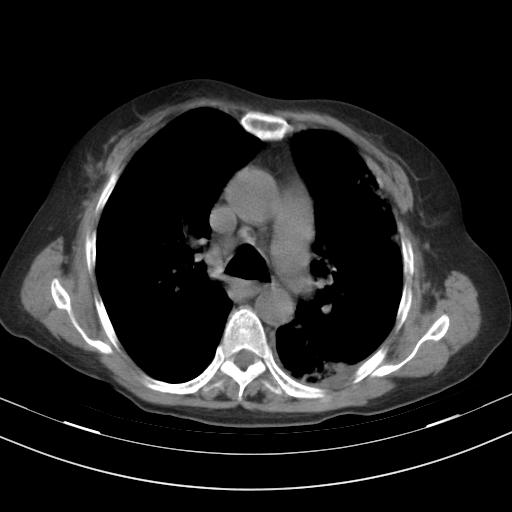

老年女性,嗜睡3天,意识模糊。轻咳,无发热。

1)两肺感染性病变;建议抗炎治疗后复查。2)纵隔淋巴结肿大。3)左侧胸腔积液。

2)纵隔淋巴结肿大。